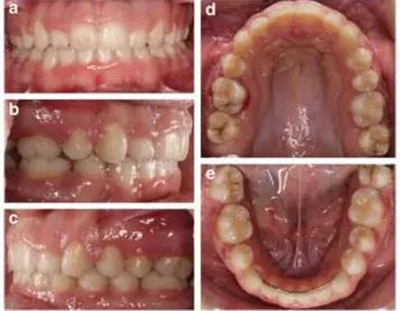

治療結(jié)果

雙側(cè)I類尖牙和磨牙關(guān)系;完全的間隙關(guān)閉(用牙線確定);覆合覆蓋糾正;仍有輕度的中線偏離。頭測分析顯示,下切牙未發(fā)生舌側(cè)移動。